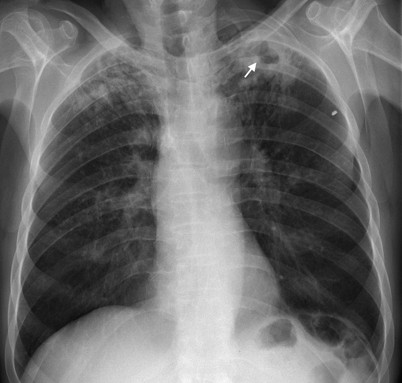

Sammlung Radiologie Tuberkulose

Sammlung Radiologie Tuberkulose from www.mevis-research.de